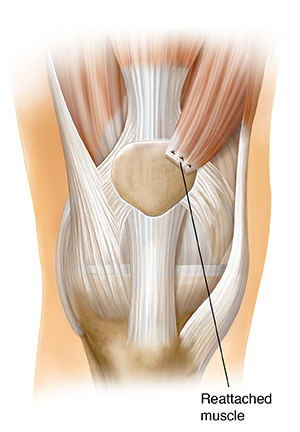

Moving a quadriceps muscle (quad transfer)

This procedure balances pull from the upper leg and is done through open surgery. Part of the muscle is detached. Then it's reattached at a new place on the kneecap.